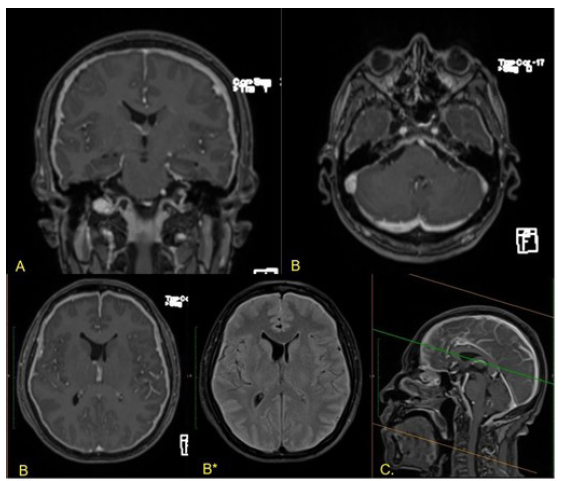

Dentro de los estudios iniciales se evidenció proteína C reactiva (PCR) aumentada (120 mg/l); hemograma, función renal, glucosa sérica y electrolitos normales; estudios para enfermedades infecciosas crónicas negativos (VIH, tuberculosis, hepatitis B, hepatitis C y sífilis); se realizó tomografía de cráneo simple (TAC) sin alteraciones; y se complementó el estudio con una resonancia magnética nuclear (RMN) simple y contrastada, en la que se documentaron signos de paquimeningitis (figura 1).

Resonancia magnética de cerebro con contraste

Figura 1: Resonancia magnética de cerebro con contraste

Nota: secuencias potenciadas en T1 posterior a la administración de contraste en planos Coronal (A), axial (B) y sagital (C), asociado a corte axial en secuencia FLAIR (B*) en las que se evidencia engrasamiento paquimeníngeo difuso, bihemisférico e infratentorial, con espesor máximo de 4mm frontal bilateral, sin otros hallazgos anormales.

Fuente: elaboración propia.